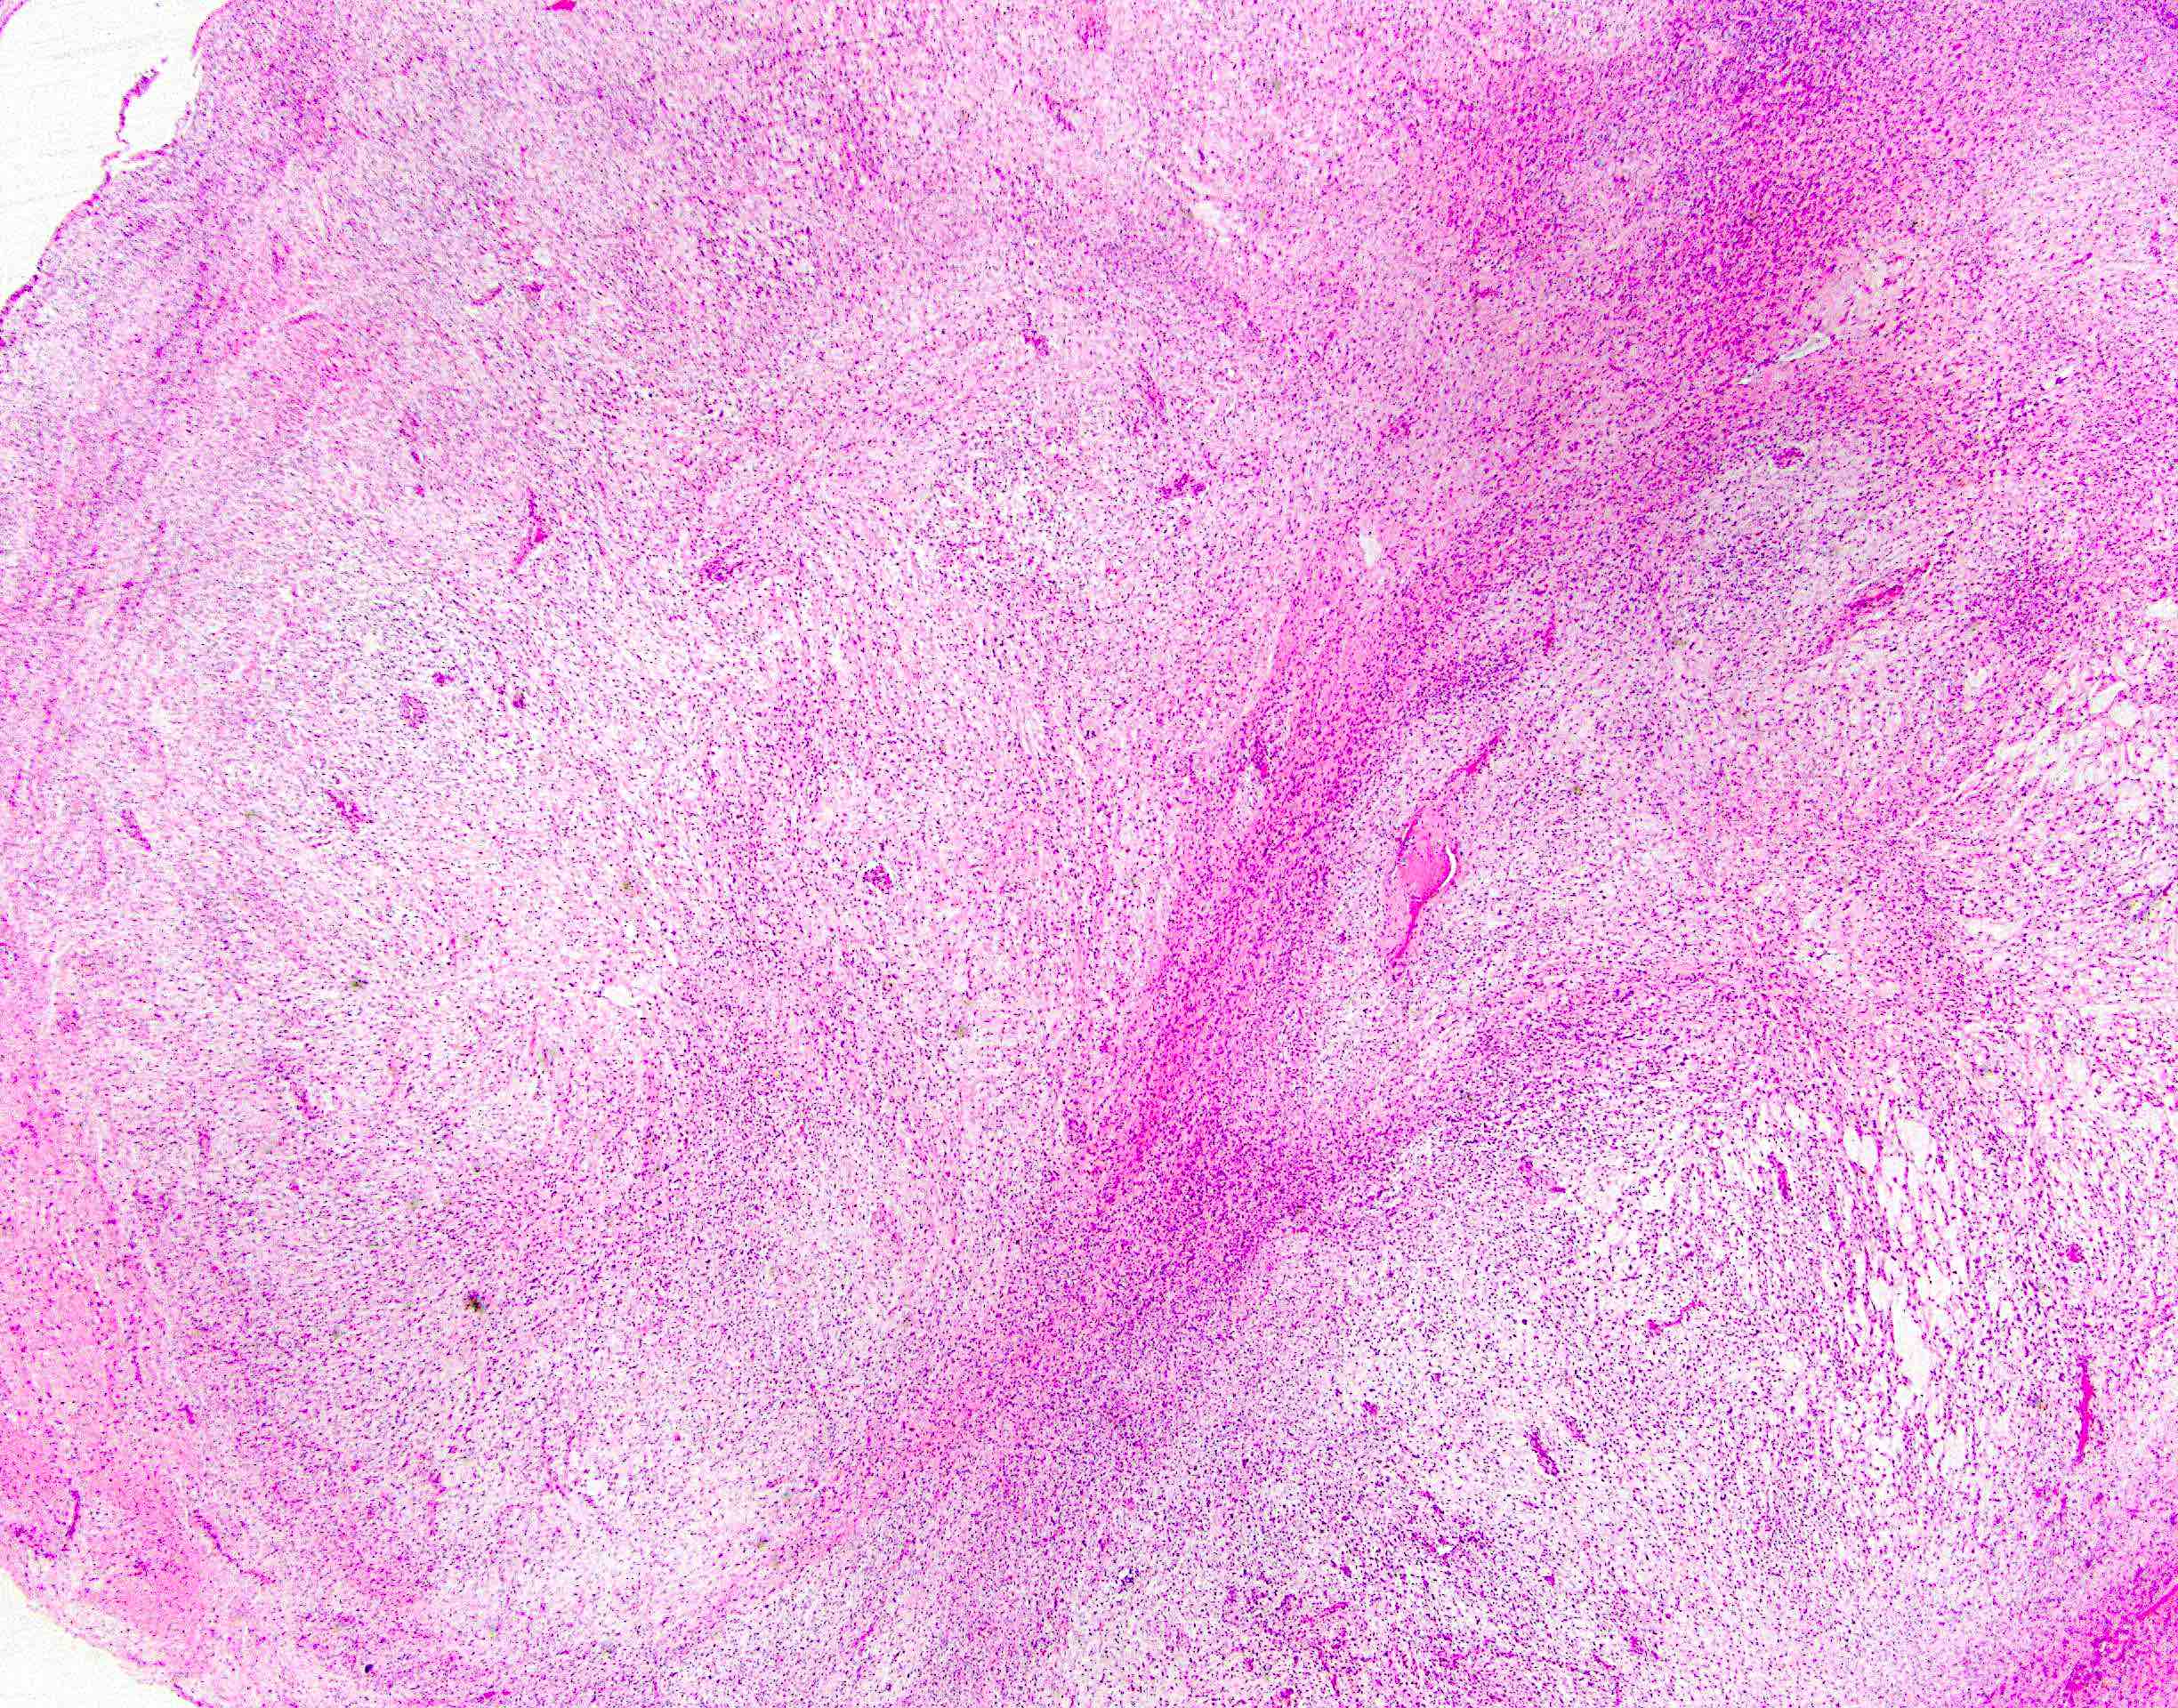

Microscopic (histologic) description

- Low to moderately cellular, bland fusiform or spindled cells with focal to diffuse whirling in heavily collagenized stroma with abrupt transition to myxoid areas

- 45% have epithelioid areas

- 40% contain poorly formed but large collagen rosettes

- Often infiltrates adjacent skeletal muscle

- Occasionally has areas of increased cellularity, atypia, necrosis or mitotic activity characteristic of intermediate to high grade sarcoma

- Recurrences may show increased cellularity and mitotic activity

Microscopic (histologic) images